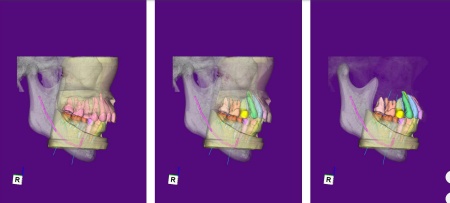

まずは、口腔内全体の矯正治療から開始します。

上顎は左上の歯が欠損していたため、左右のバランスを整える目的で、右上の歯(第1小臼歯)を抜きました。

その後、ワイヤー矯正とクローズドコイル(バネの装置)を使ったスピード矯正を行い、前歯を後方に移動させます。

下顎は残根も利用しながら、矯正用の小さなネジ「テンポラリーインプラント(インプラントアンカー)」を顎の骨に埋め込んで固定源とする方法も併用し、歯を移動させました。